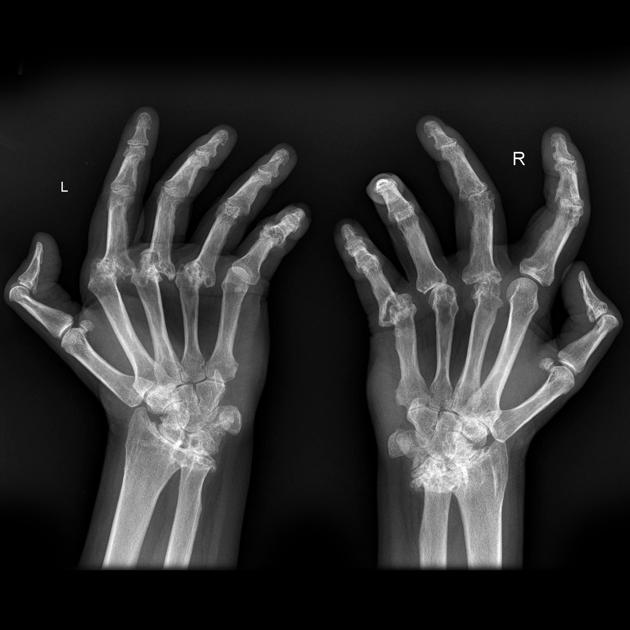

Example 4

Diagnosis

Rheumatoid Arthritis of the hands

Image 4: Stanislavsky, A., Yap, J. Rheumatoid arthritis (musculoskeletal manifestations). Reference article, Radiopaedia.org.https://doi.org/10.53347/rID-12370

Image 5: Stanislavsky, A., Yap, J. Rheumatoid arthritis (musculoskeletal manifestations). Reference article, Radiopaedia.org. https://doi.org/10.53347/rID-12370